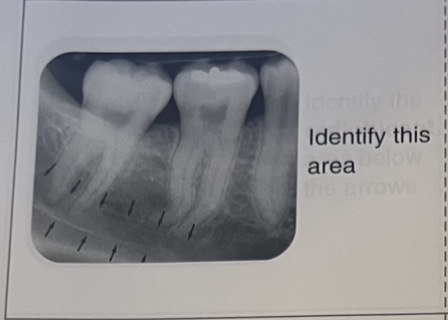

A-enamel

B-dentin

C-DEJ

Pulp chamber and pulp canal

Lámina dura

Crestal lámina dura

Periodontal ligament space